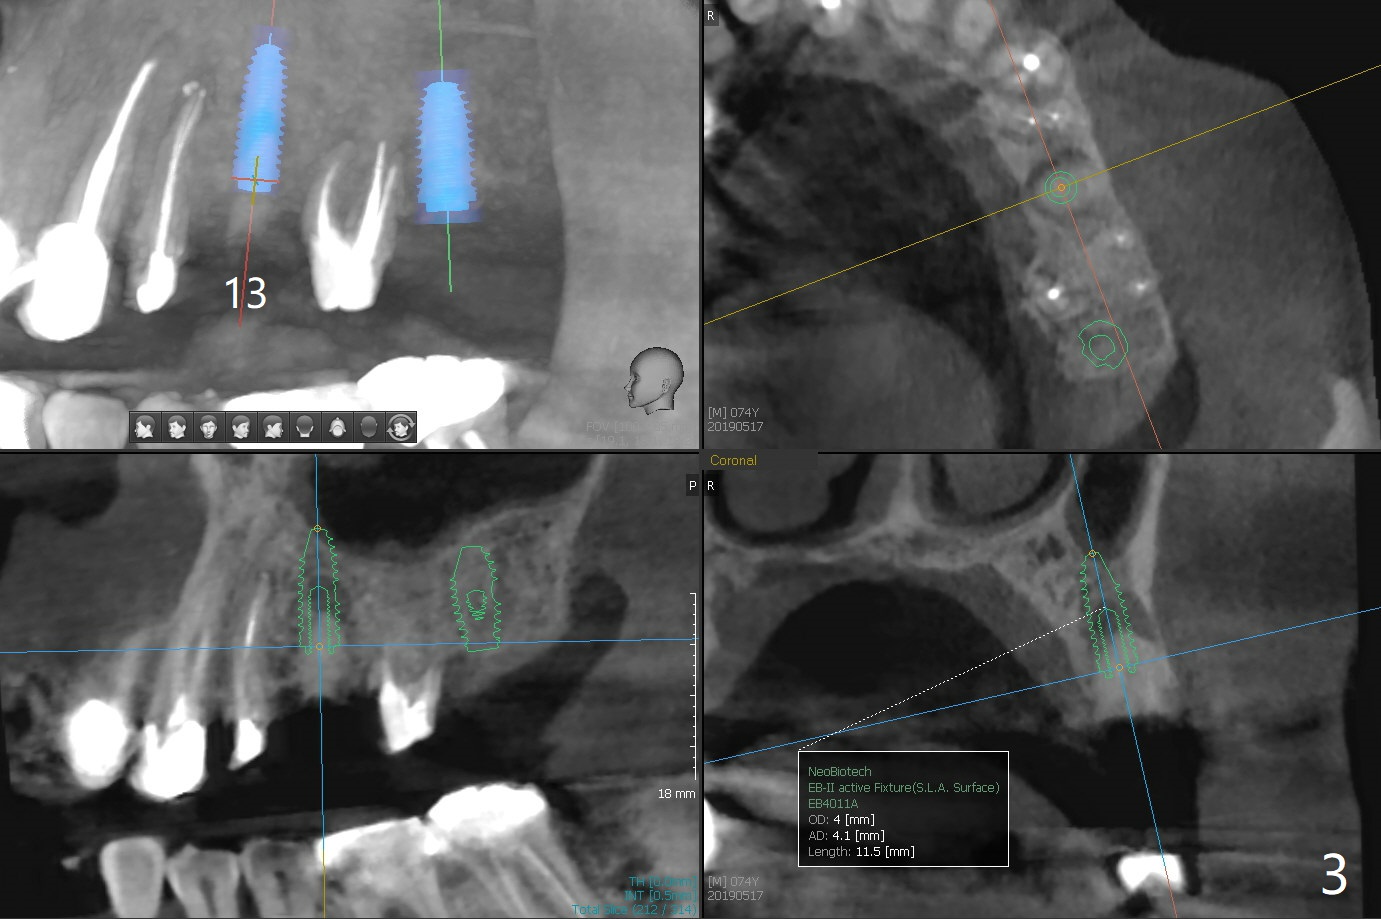

A 74-year-old man with multiple crowns and FPD needs implants at #13 and 15 (Fig.1). To avoid drills or implant (particularly immediate one) touching the neighboring root, 2.2 mm drill will reach the depth (sequentially) first and take segmental panoramic X-ray. Then return to the original sequence: diameter first and depth second to avoid bone necrosis.